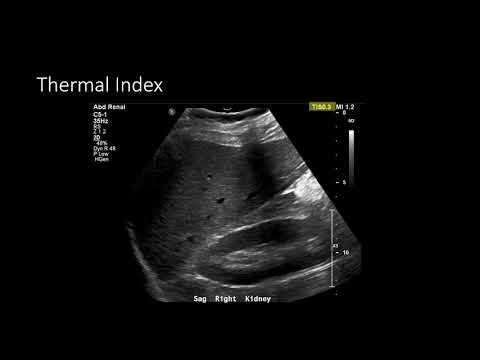

Высокоэффективные вопросы из экзаменационных работ по физике радиологии с видеоответами Идеально подходит для самопроверки перед экзаменом по физике радиологии 👇 ➡️ КОМПЛЕКС ПО РЕНТГЕНУ, УЛЬТРАЗВУКУ И МРТ (СКИДКА более 25%): ➡️ БАНК ВОПРОСОВ ПО РЕНТГЕНУ: ➡️ БАНК ВОПРОСОВ ПО УЛЬТРАЗВУКУ: ➡️ БАНК ВОПРОСОВ ПО МРТ: =========================== Я также разработал два ПУТИ ОБУЧЕНИЯ РАДИОПЕДИИ (👈 ССЫЛКА НА СКИДКУ 25%) ЧТО ВКЛЮЧЕНО? ✅Этот сериал на YouTube без рекламы ✅Постоянно обновляемые статьи Radiopaedia ✅Обзорные слайды ✅Ключевые моменты для запоминания ✅Множество контрольных тестов ✅Вопросы с краткими ответами для запоминания ✅Официальный сертификат об окончании курса Radiopaedia Скидка 25% по ссылке: ========================== Ультразвуковой луч можно разделить на две основные области: ближнее и дальнее поле. Расстояние в ближнем поле и расхождение ультразвукового луча в дальнем поле определяются шириной элемента преобразователя и частотой ультразвука. Мы также кратко обсудим боковые лепестки и лепестки решётки. В следующем докладе мы будем использовать эти концепции для управления лучом в зависимости от требований к визуализации. ========================== ПОДПИШИТЕСЬ НА МОЮ ЕЖЕМЕСЯЧНУЮ РАССЫЛКУ 👉 Не уверены, подходят ли вам эти вопросы? Если вы здесь, то, вероятно, готовитесь к экзамену по физике в радиологии. Последние несколько месяцев я собирал работы из разных стран, отбирая наиболее часто задаваемые вопросы. Вы удивитесь, как часто вопросы повторяются! Типы вопросов, задаваемых в экзаменах FRCR, RANZCR AIT, ARRT, FC Rad Diag (SA), ABR Qualifying Core Physics и MICR Part 1, удивительно похожи, а ключевые концепции остаются неизменными. Я взял самые сложные вопросы и ответил на них в видеоформате, чтобы объяснить, почему одни ответы верны, а другие — нет. Удачной учёбы, Майкл #радиология #радиология #FOAMrad #FOAMed